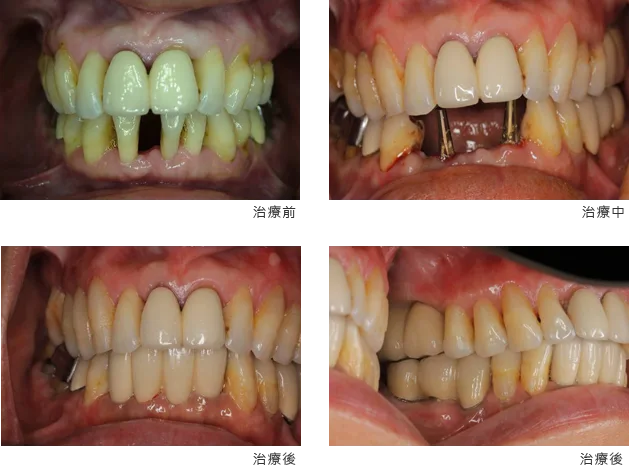

[ 賴先生植牙案例 ]